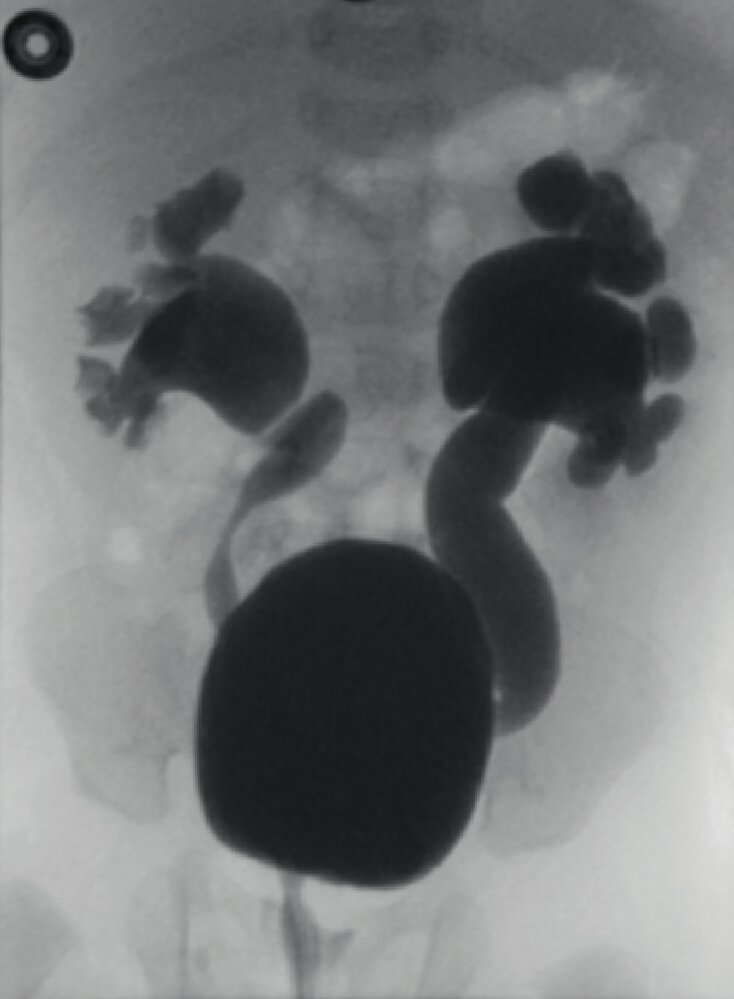

Voiding cystourethrography [2][5][14]

• Only used if there is high suspicion for VUR because of its invasive nature and use of radiation

• Potential findings include:

• Visualization of VUR (see ā€œDiagnostics of VURā€) [2][3]

• Obstructive uropathy (e.g., stenosis, hydronephrosis)